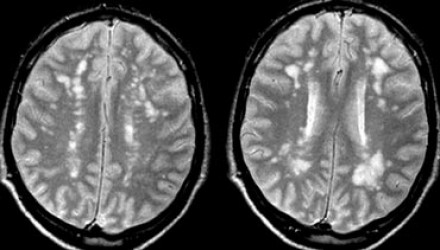

圖片六:白質(zhì)病變,F(xiàn)azekas分級為I、II 、III級

衰老過程出現(xiàn)白質(zhì)變化的臨床意義尚未完全闡明。多個腦血管危險因素與白質(zhì)病變有關(guān),除高血壓之外,其中最強的危險因素就是衰老。是否是生理性的白質(zhì)變化,取決于患者的年齡。

根據(jù)Fazekas評分量表,可將白質(zhì)變化分為不同的程度:

1. 輕度:點狀白質(zhì)損傷病灶,F(xiàn)azekas分級為I級。

2. 中度:融合的白質(zhì)損傷病灶,F(xiàn)azekas分級為II 級,在深部白質(zhì)中出現(xiàn)這種病灶可以認為是衰老過程中的正常生理性改變。

3. 重度:廣泛融合的白質(zhì)損傷病灶,F(xiàn)azekas分級III級,這種改變是病理性的。